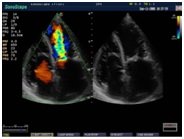

• многостороннее исследование сердца, при помощи специального набора кардиологических функций;

• автоматический сегментный анализ движения миокарда;

• тканевой допплер;

• CW допплер на линейных датчиках;

• режим замедленной перемотки для тщательного исследования работы сердца;